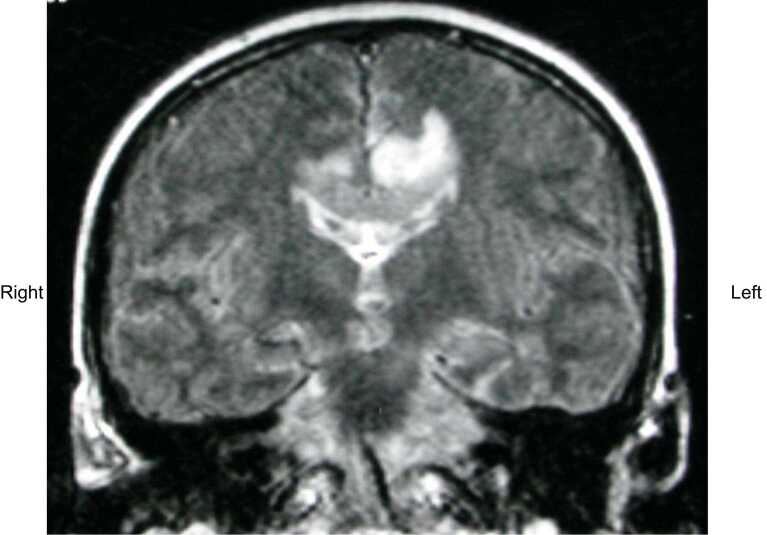

The authors report a case of varicella zoster encephalitis, mimicking a glioblastoma on Magnetic Resonance Imaging (MRI) and Magnetic Resonance Spectroscopy (MRS). The limitations of MRI/MRS, may lead to delayed treatment with antiviral agents, which can result in increased morbidity and mortality. The possibility of viral encephalitis should remain in the differential diagnosis of all patients presenting with headaches and confusion, even when imaging results are indicative of a neoplastic process.

Abstract Image